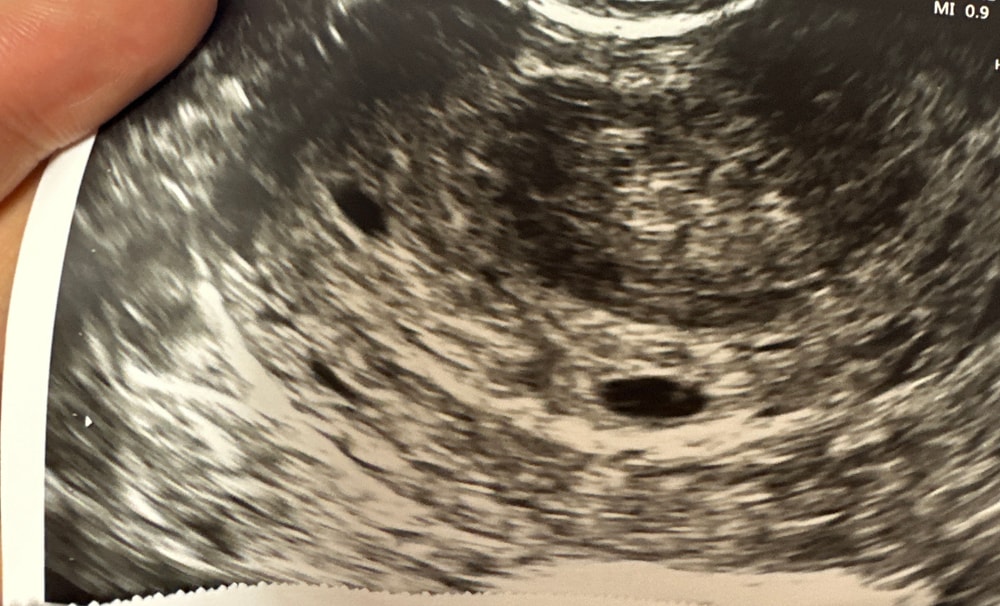

Похоже на два🙂так же как у меня,просто они были побольше на момент узи

Да, похоже на два отдельных плодных, в динамике будет понятно оба ли будут с вами, растите 💖

Я склоняюсь к тому что это два плодных яйца 😍❤️❤️ поздравляю вас, пусть всё идёт благополучно 🌺

Да, это 2 плодных яйца. Через неделю уже можно увидеть эмбрионы и сердцебиение их

Конечно два ❤️❤️ поздравляю вас)

Это оказалась не двойня) сегодня на узи одно ПЯ и один эмбрион

В 6 недель увидели 2 плодных яйца и сб +.